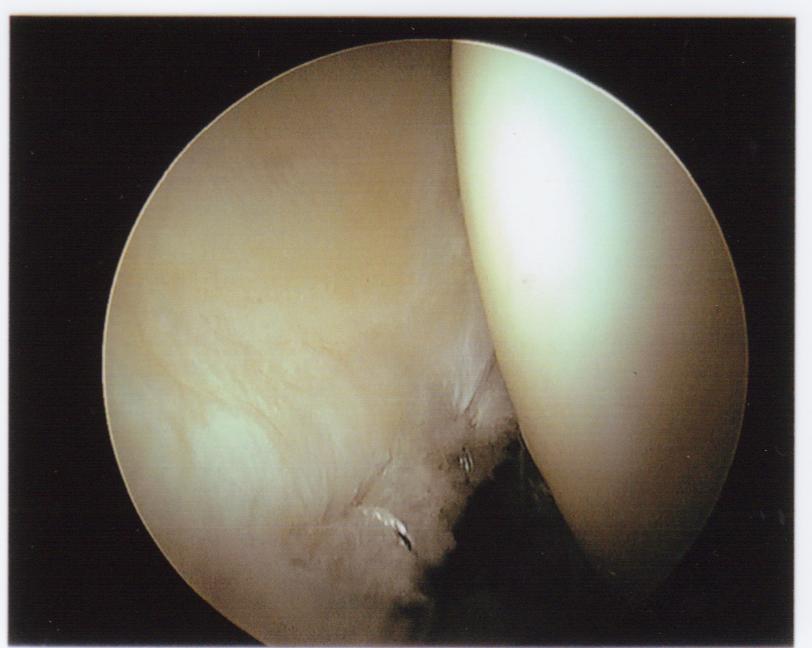

Move on if you’re squeamish. Otherwise, here are photos from my first arthroscopic hip surgery, in July 2011.